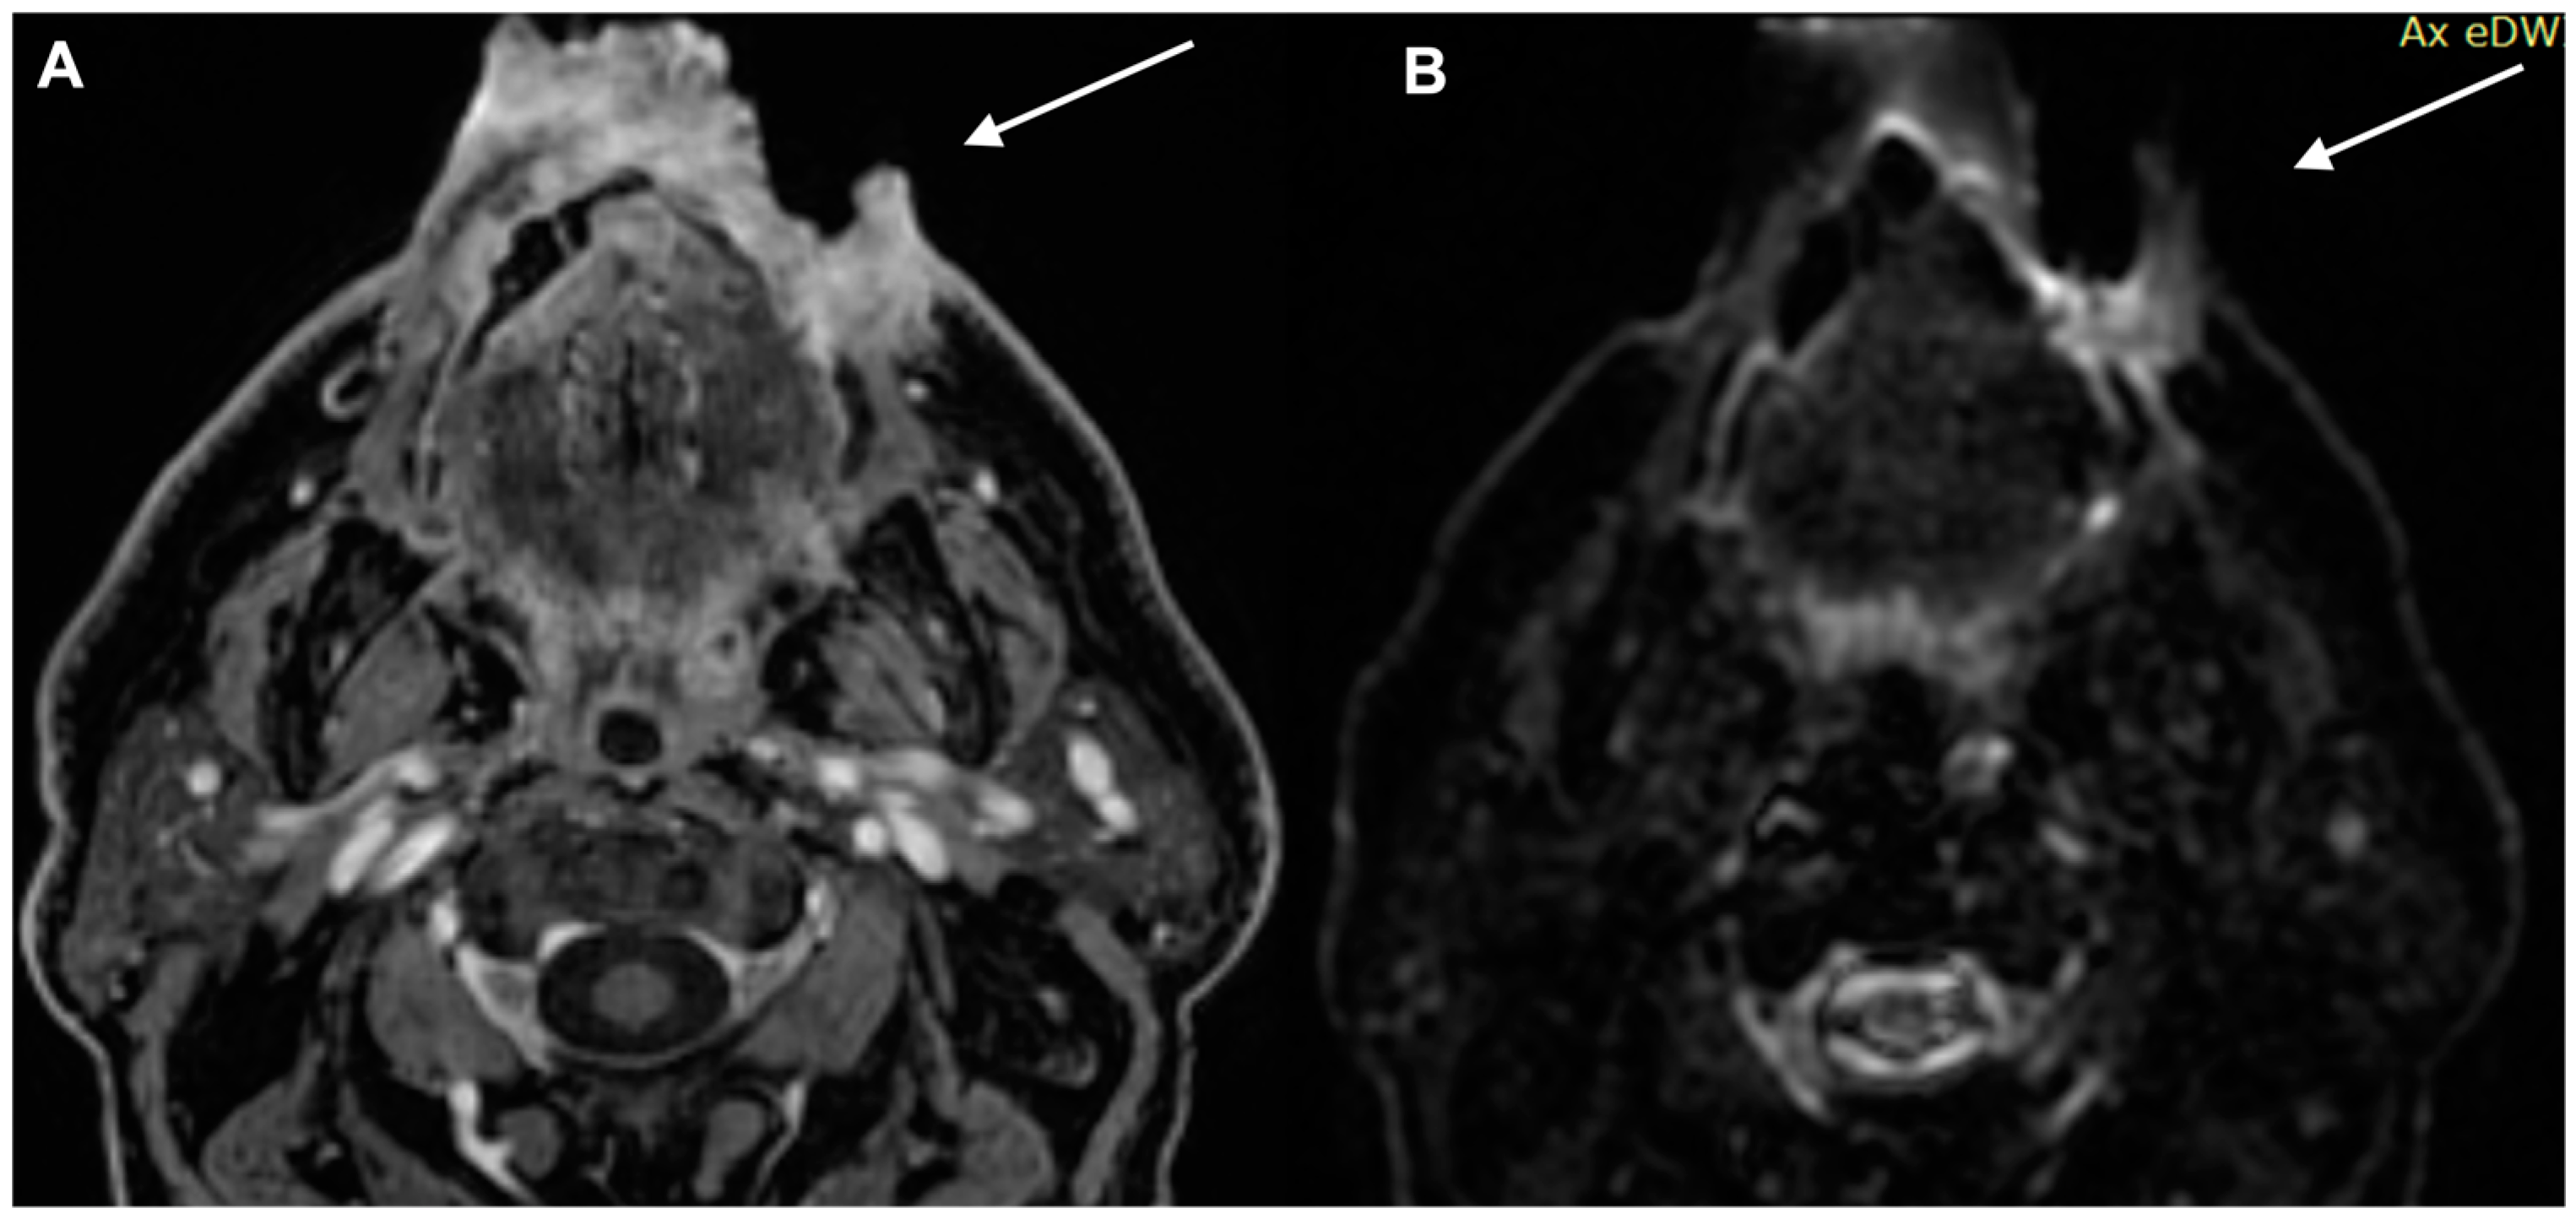

- Kawaguchi, M.; Kato, H.; Suzui, N.; Miyazaki, T.; Tomita, H.; Hara, A.; Matsuyama, K.; Seishima, M.; Matsuo, M. Imaging findings of cutaneous angiosarcoma of the scalp: Comparison with cutaneous squamous cell carcinoma. Neuroradiol. J. 2021, 34, 329–334. [Google Scholar] [CrossRef]

- Kawaguchi, M.; Kato, H.; Tomita, H.; Hara, A.; Suzui, N.; Miyazaki, T.; Matsuyama, K.; Seishima, M.; Matsuo, M. Magnetic Resonance Imaging Findings Differentiating Cutaneous Basal Cell Carcinoma from Squamous Cell Carcinoma in the Head and Neck Region. Korean J. Radiol. 2020, 21, 325–331. [Google Scholar] [CrossRef] [PubMed]

- Kawaguchi, M.; Kato, H.; Tomita, H.; Hara, A.; Suzui, N.; Miyazaki, T.; Matsuyama, K.; Seishima, M.; Matsuo, M. MR imaging findings for differentiating cutaneous malignant melanoma from squamous cell carcinoma. Eur. J. Radiol. 2020, 132, 109212. [Google Scholar] [CrossRef] [PubMed]

- Sheng, M.; Tang, M.; Lin, W.; Guo, L.; He, W.; Chen, W.; Li, K.; Liu, J.; Xiao, C.; Li, Y. The value of preoperative high-resolution MRI with microscopy coil for facial nonmelanoma skin cancers. Ski. Res. Technol. 2021, 27, 62–69. [Google Scholar] [CrossRef]